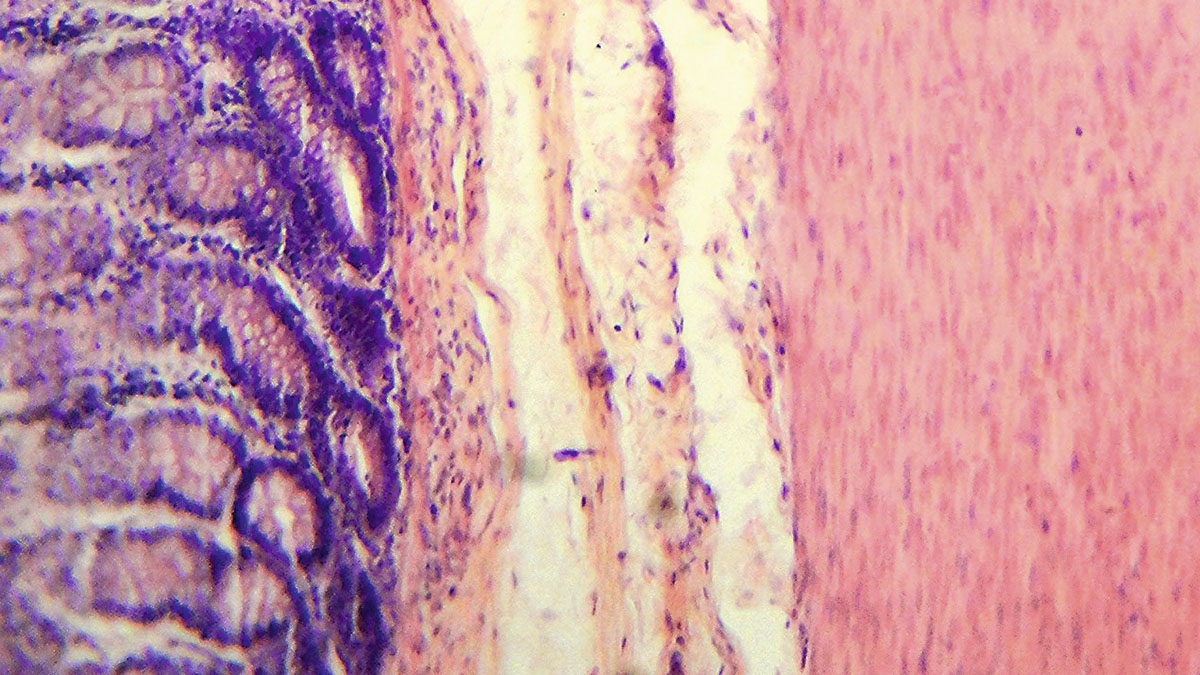

Suolisto on suuri elin, jota asuttaa arvioiden mukaan jopa sata biljoonaa suolistomikrobia, tuhansia eri lajeja. Jos suolen kaikkine poimuineen levittäisi auki, pinta-ala vastaisi tenniskenttää. Kaikki nämä pinnat ovat mikrobien peitossa.

Suolen ekosysteemin kannalta erittäin hyödyllisiä bakteerilajeja ovat sellaiset, jotka tuottavat lyhytketjuisia rasvahappoja. Ne käyttävät ravinnokseen kuituja. Lyhytketjuiset rasvahapot hyödyttävät ja ravitsevat myös suolen seinämän epiteelisoluja.

– Matala-asteisessa tulehduksessa tietyt bakteerisuvut pääsevät liian suureen rooliin suolistossa ja aiheuttavat tulehdusta. Suolen seinämä heikkenee ja suoli alkaa vuotaa muualle elimistöön suolen sisältöä, jota sinne ei pitäisi päästä, ja immuunipuolustus reagoi tähän, Kainulainen selittää.